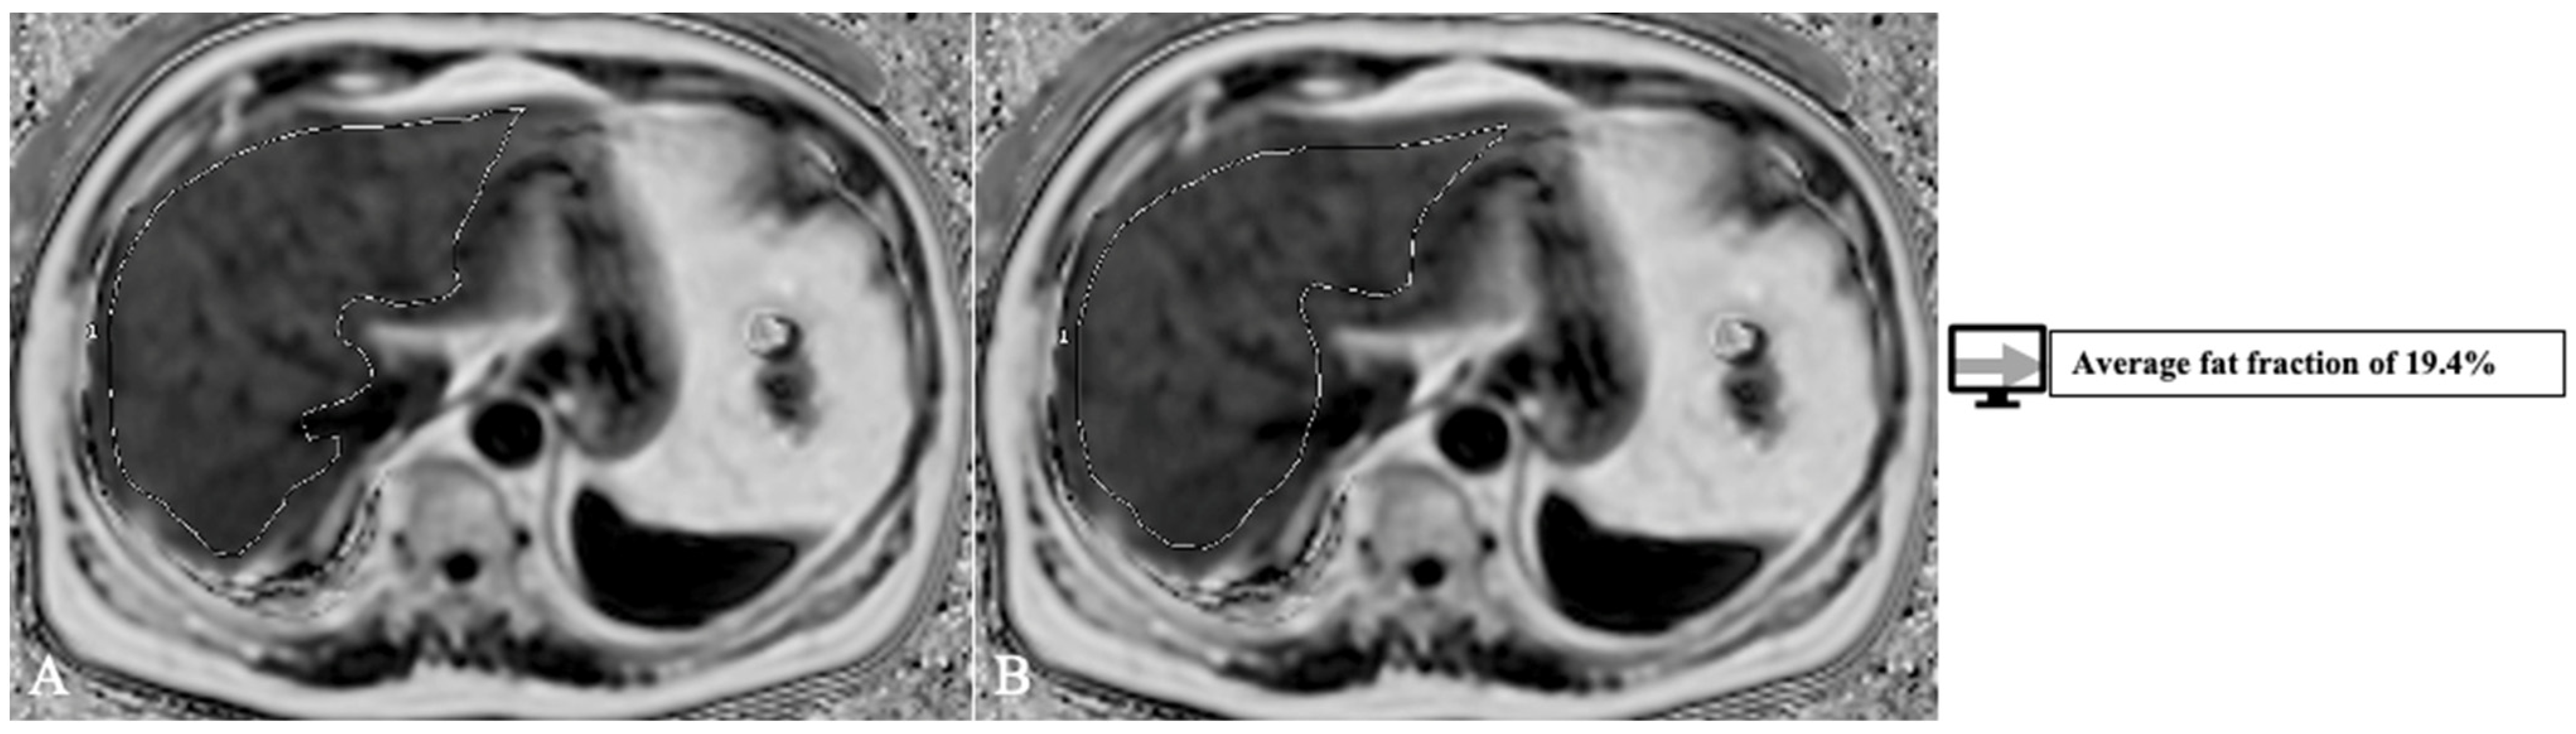

4.2. Segmentation

| Jimenez-Pastor et al. [69] | 2021 | Liver segmentation, fat, and iron quantification | MRI | DL (CNN) | 93% |